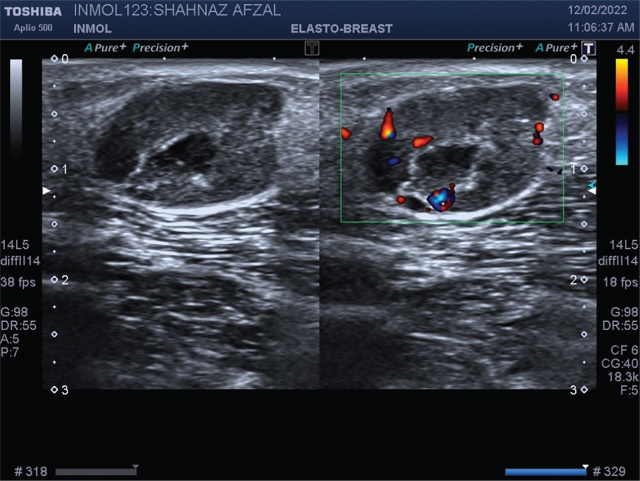

Case presentation: We report a middle-aged female patient, with known case of hypopharyngeal squamous cell carcinoma, who initially showed partial response to chemoradiotherapy but developed cutaneous nodules in the region of the right axilla and bilateral lateral chest wall posterior to the posterior axillary fold. Excision biopsy of one of these nodules showed metastatic squamous cell carcinoma. The patient was again referred to the Oncology Department of INMOL Hospital and her chemotherapy was planned for cutaneous metastasis.